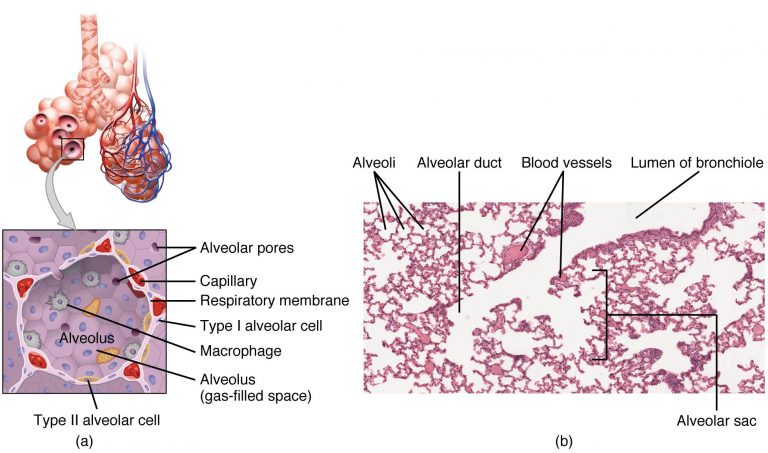

1 – Review of Respiratory System Anatomy

For distinction from neonatal respiratory distress syndrome, acute respiratory distress syndrome was also labelled as adult respiratory distress syndrome (ARDS). It involves inflammation in the lung parenchyma, increased alveolar permeability, reduced lung compliance and non-functional gas exchange. The increased alveolar permeability allows fluid to build up which in-turn prevents the lungs from filling up air, causing less oxygen in the bloodstream. The oxygen deprivation sequentially leads to organ failure. Low blood-oxygen levels in the bloodstream not only affects the lungs but, also harms other organs in the body and prevents oxygen from reaching them for normal functioning. The intensity of the disease can be determined by measuring and comparing blood-oxygen levels. ARDS is a rapidly developing and potentially fatal lung disease, most people don’t survive ARDS. ARDS survivors mostly have lasting damage to their lungs. The risk of death and the severity of the disease increases with age. The main symptom of ARDS is distressing shortness of breath, which develops within the first couple hours and lasts longer than the illness and the duration of recovery.

Type I: – involves a ventilation/perfusion mismatch that causes untreatable hypoxemia (PaO2). Another characteristic of type I respiratory failure is alveolar flooding.